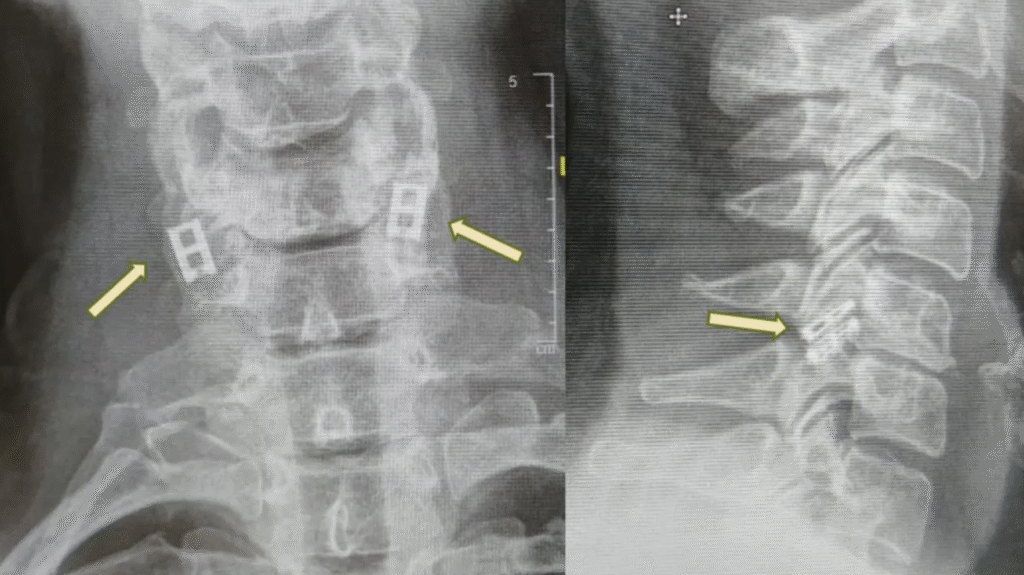

Actualmente, las lesiones de médula espinal no tienen cura completa, por lo que el tratamiento se centra en estabilizar al paciente, prevenir daños mayores y maximizar la función. La atención de emergencia suele implicar inmovilizar la columna vertebral, reducir la inflamación y, en ocasiones, realizar cirugía para reparar fracturas o aliviar la presión.

A diferencia de otros tejidos, las neuronas de la médula espinal no pueden regenerarse de forma natural y, con el tiempo, el tejido cicatricial bloquea las señales restantes. El nuevo procedimiento busca reemplazar la sección dañada con una médula espinal cultivada en laboratorio que se fusiona con tejido sano por encima y por debajo de la lesión. Estudios en ratas han mostrado resultados notables, con animales que recuperan la capacidad de caminar con normalidad.

El procedimiento comienza con células sanguíneas del paciente, que se reprograman para convertirlas en células similares a células madre, capaces de transformarse en cualquier tipo celular. También se recolecta tejido graso para crear un andamiaje de hidrogel personalizado, en el que las células similares a células madre se convierten en una estructura de médula espinal. Este tejido diseñado se implanta, reemplazando las áreas cicatrizadas y reconectando el sistema nervioso.